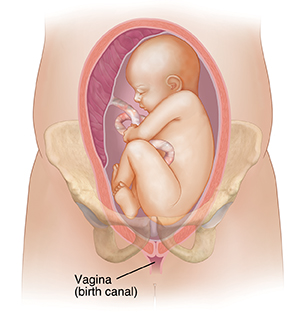

Breech presentation means that your baby is in a buttocks-first or feet-first position. Babies are usually in a head-first position. A breech position can make it hard for the baby’s head to fit through the birth canal during delivery. This can cause lack of oxygen or nerve damage in your baby.

Complete breech. The baby's knees are bent, and the feet and buttocks are closest to the birth canal.

| Complete breech. |